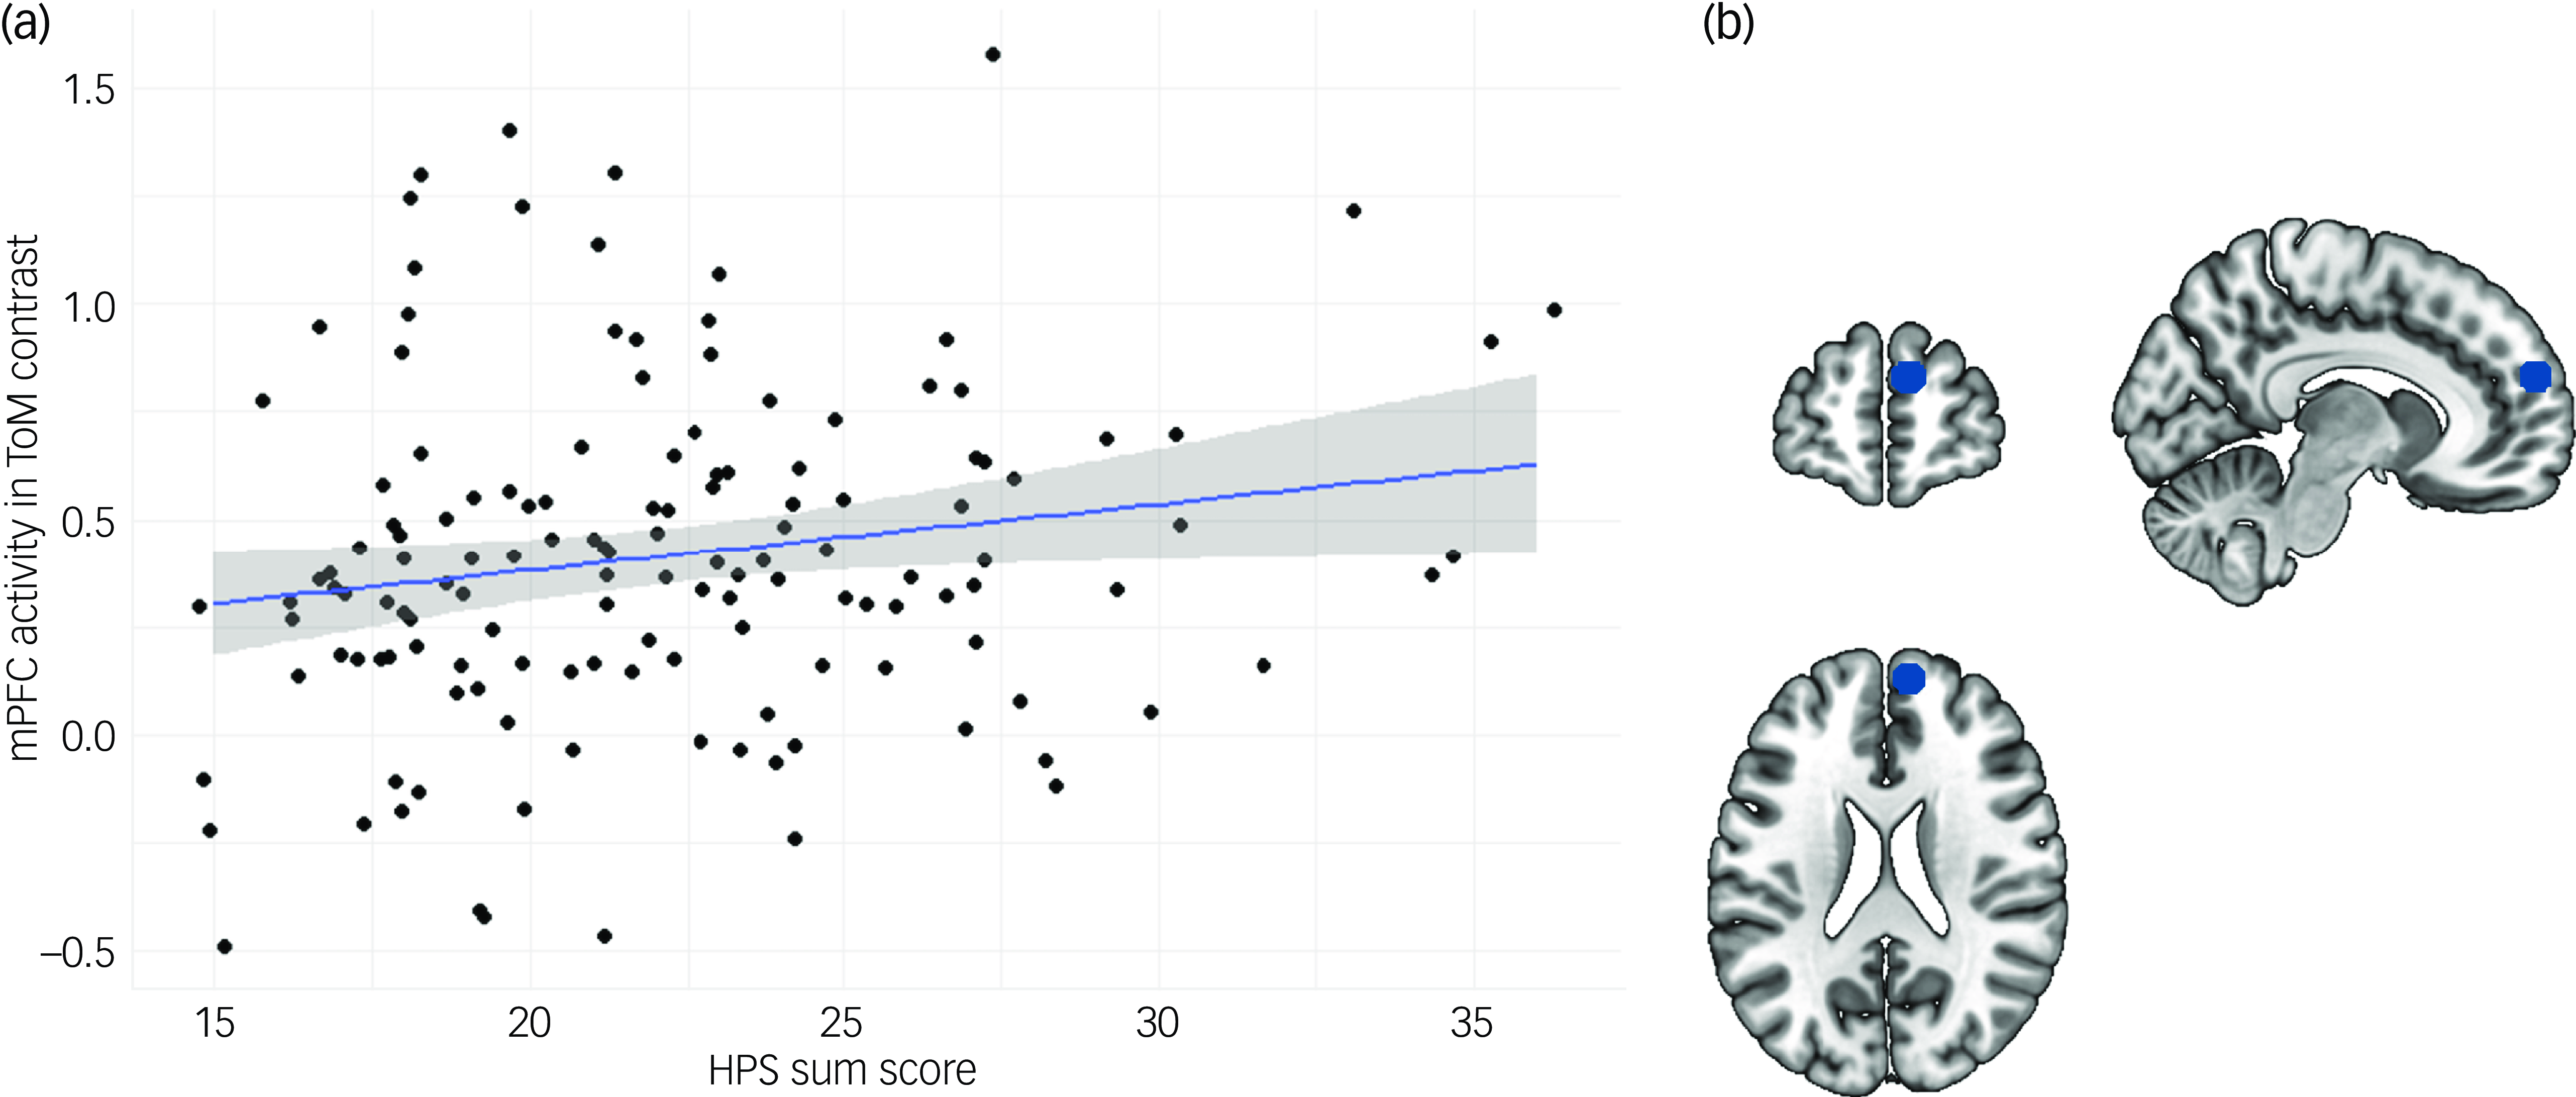

Linear regression analyses revealed a significant effect of the HPS sum score on neural activity in the ToM contrast in the right mPFC (β = 0.171, P = 0.046; Fig. 2). There were no significant effects of the HPS on neural activity in any of the other ToM ROIs (P s = 0.166–0.948). Results from exploratory whole-brain analyses indicate further ToM-related neural activity to be positively associated with the HPS, mainly located in a cluster in the rostral anterior cingulate cortex (ACC) (x = 3, y = 33, z = 6; k = 31, voxel level: P < 0.001; Fig. 3 and Table S2). Analyses yielded no significant results regarding the effect of the HPS on behavioural ToM performance (P = 0.582).

Fig. 2 Results from linear regression analyses on hypomanic personality traits on theory of mind (ToM)-related neural activity. (a) Scatter plot depicting the association between the Hypomanic Personality Scale (HPS) sum score and neural activity in the right medial prefrontal cortex (mPFC) in the ToM contrast of the EmpaToM paradigm. (b) Schematic depiction of ToM region of interest (ROI) in the right mPFC.

Analyses revealed hypomanic personality traits to be positively associated with ToM-related neural activity in anterior rostral parts of the right mPFC. Additionally, exploratory whole-brain analyses revealed a positive association between hypomanic personality traits and ToM-related neural activity mainly located in the rostral ACC. Behavioural ToM performance did not show significant associations with hypomanic personality traits. Regarding behavioural or neural measures of empathy, results do not support the notion of elevated empathy in hypomanic personality. However, self-reported empathic concern as another aspect of social affect was positively associated with hypomanic personality traits.

Our findings on ToM-related neural activity in the mPFC and ACC can be discussed in consideration of previous findings of these brain regions’ functional associations. The mPFC and ACC have been associated with cognitive functions related to working memory, decision-making and cognitive flexibility. Reference Jobson, Hase, Clarkson and Kalaria33 As for the mPFC as a central hub in social cognition, anterior rostral compared with more posterior parts have shown activation in social cognition tasks, comprising self-knowledge, person perception and mentalising. Reference Steele and Lawrie34 Although the adjacent ACC is included in most reviews on the mPFC, in more specific investigations, activity in the rostral ACC has been reported to be associated with social information processing. Reference Etkin, Egner, Peraza, Kandel and Hirsch35 This is supported by animal studies showing ACC lesions to lead to reduced interest in acquiring social information. Reference Rudebeck, Buckley, Walton and Rushworth36 Taken together, our findings correspond to previous findings on the rostral mPFC’s and ACC’s functional associations related to social cognition.

Potential implications of these findings on aberrant neural activity for bipolar disorder risk are to be evaluated in the light of no differences in behavioural measures. Conceivably, elevated frontal brain activity during ToM requirements could be indicative of higher amounts of resources required to achieve the same behavioural outcome. Reference Rudebeck, Buckley, Walton and Rushworth36 When evaluating potential underlying mechanisms, it is important to note that our results do not indicate the hypothesised negative but a positive association with bipolar disorder risk. In contrast to a lower ToM in people with bipolar disorder, on which we based our hypotheses, elevated activity might be indicative of an adaptive compensation of predisposition to risk, enabling unimpaired behavioural outcomes. Put differently, bipolar disorder risk-related proneness to show impaired ToM performance might be partly resolved or counteracted by higher cognitive effort, reflected in elevated neural activity.